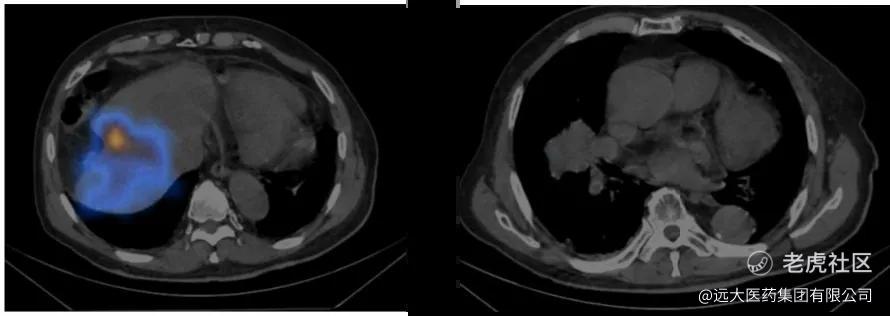

如图1~图6所示,肝及肺内蓝黄色为钇-90沉积区域,亮度越高,表明吸收剂量越大,随着治疗后时间的延长可以看到颜色的亮度逐渐减弱。

(左:图1 SIRT后肝扫描(2h);右:图2 SIRT后肺扫描(2h))